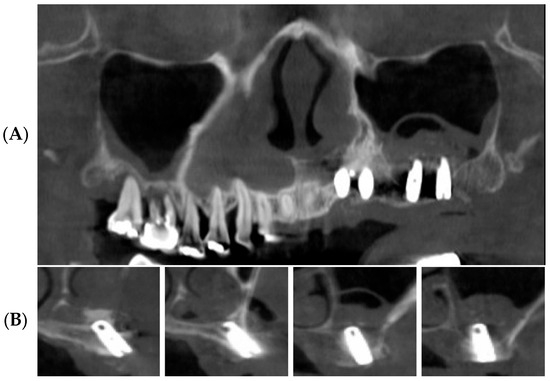

3.2. Radiographic Results